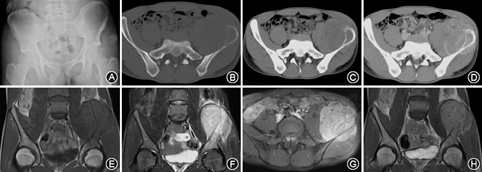

骨质改变:13例中9例表现为单纯溶骨性破坏,4例为混合型(图1A、图2A),其中3例肿瘤内见絮状骨化,1例为针状;4例见骨质膨胀性破坏,2例见骨性分隔,2例见骨皮质中断,6例见局部骨质硬化。3例见骨膜反应。软组织肿块:6例可见。

骨质改变:13例中3例表现为单纯溶骨性破坏,10例为混合型,其中8例肿瘤内絮状骨化,2例为针状,骨化较少;10例见骨质膨胀性破坏,3例见骨性分隔,12例见骨皮质中断,11例见局部骨质硬化。骨膜反应:10例可见,其中5例为层状并见Codman三角,5例为放射状。软组织肿块:13例均可见,呈等或稍低密度,其中5例边界较清晰,4例周围软组织受压。5例见不完整的骨包壳(图1B,图1C,图1D、图2B,图2C,图2D)。4例增强扫描后不均匀强化(图1D、图2D)。

骨质改变:13例中均见明显骨质破坏,T1WI为低信号,T2WI为混杂高信号,骨髓水肿,边界模糊。肿瘤内骨化显示欠清。骨膜反应:显示模糊,2例见放射状骨膜反应,5例见层状骨膜反应,T1WI及T2WI均为低信号。软组织肿块:13例均可见,病变范围大于CT和X线平片,T1WI呈等或低信号,T2WI呈混杂高信号,其中5例见斑片长T1长T2信号区(病理为液化坏死),8例软组织肿块边缘清晰,9例肿块边缘见不完整的线样低信号(病理为假包膜),周围软组织局部受侵(图1E、图1F,图2E、图2F)。10例见软组织肿块周围水肿信号。4例MRI增强扫描后不均匀强化(图1G,图2G、图2H)。

大体标本5~15 cm,肿瘤软、脆,呈粉红或灰白色伴有骨质破坏及软组织肿块,5例可见液化坏死区,呈半流体状。9例可见不完整假包膜。镜下可见均匀一致的小圆形未分化肿瘤细胞,胞质少,细胞边界不清,胞核圆形,染色质呈斑点状(图1H)。免疫组化CD99(+)13例,CD56(+)、PAS(+)、Vim(+)各11例,Ki-67(+)10例,S-100(+)、NSE(+)各5例、Syn(+)3例、CgA(+)2例。